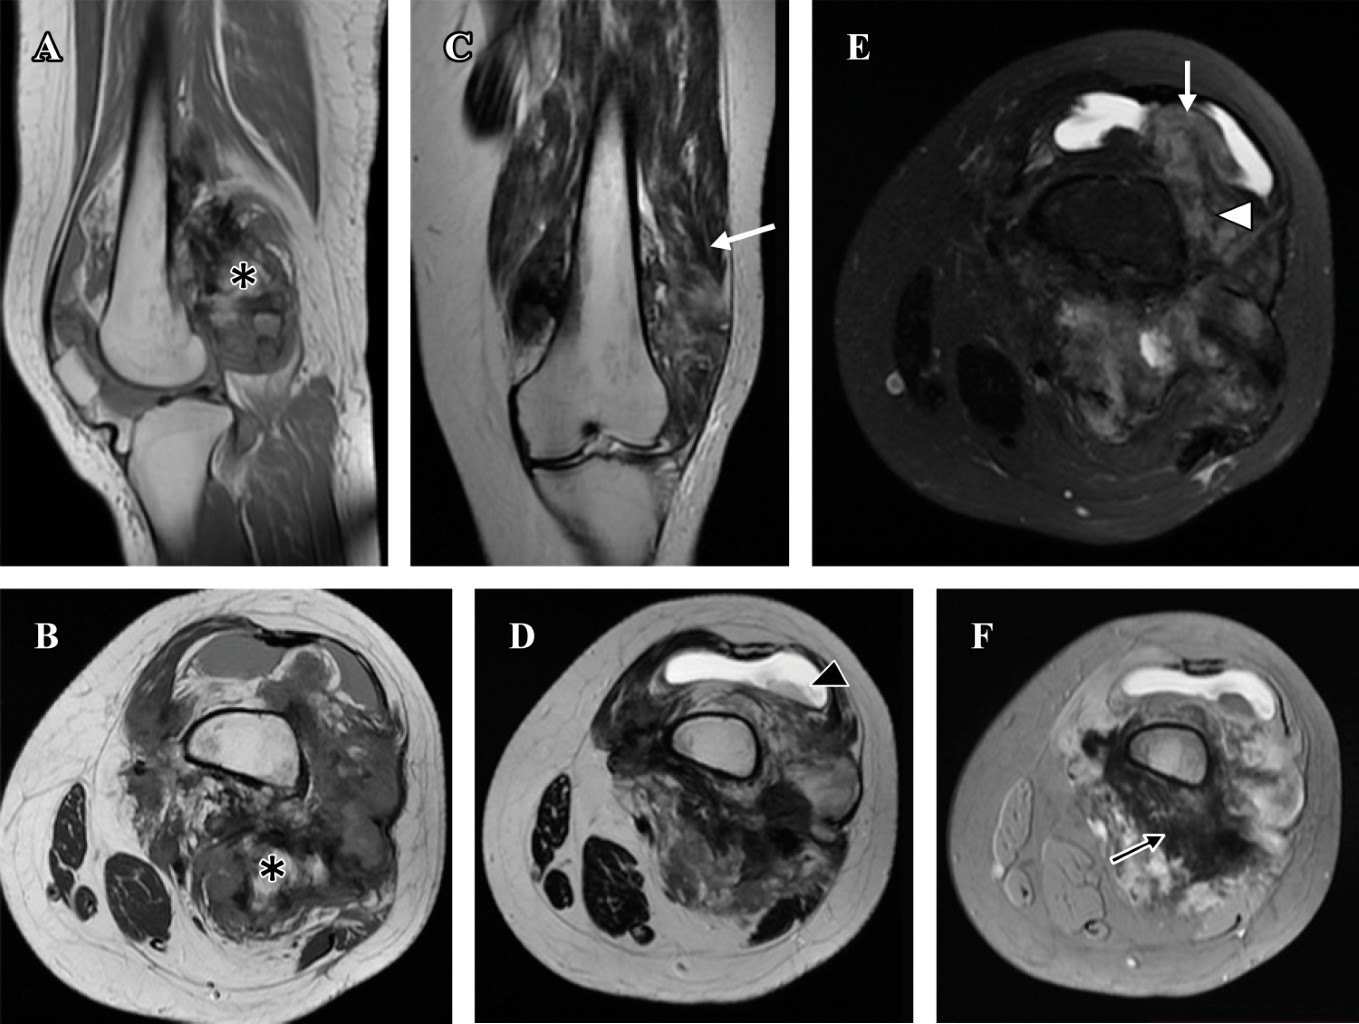

Osteosarcoma parosteal con componentes de condrosarcoma y liposarcoma de bajo grado. Una variante histológica poco frecuente. Reporte de caso y revisión de la literatura

Introducción: el osteosarcoma parosteal convencional es un tumor óseo maligno poco común, que comprende el 4% de todos los osteosarcomas. Aunque es poco común, el osteosarcoma parosteal es el tipo más común de osteosarcoma de la superficie ósea. Presentamos las características clínicas, histológicas y de imagen de una variante histológica rara de un osteosarcoma parosteal, revisamos la literatura y enfatizamos la importancia de la correlación radio-patológica, así como la interpretación de una biopsia representativa para obtener el diagnóstico correcto. Reporte de caso: mujer de 36 años inició su cuadro un año antes de su ingreso al hospital con aumento de volumen en rodilla izquierda y dolor. Los estudios de imagen mostraron una tumoración heterogénea yuxtacortical localizada en la superficie posterior de la metáfisis femoral distal. Se realizó biopsia incisional, con diagnóstico de osteosarcoma parosteal y se realizó resección quirúrgica amplia. De acuerdo con los hallazgos de la pieza quirúrgica se realizó el diagnóstico de osteosarcoma parosteal con componentes de condrosarcoma y liposarcoma de bajo grado. El conocimiento de esta rara variante de osteosarcoma parosteal puede llevar a los ortopedistas oncólogos a considerar otros componentes y proporcionar márgenes quirúrgicos adecuados. Conclusión: presentamos las características clínicas, histológicas y de imagen de un osteosarcoma parosteal con componentes de liposarcoma y condrosarcoma de bajo grado.

Figura 1